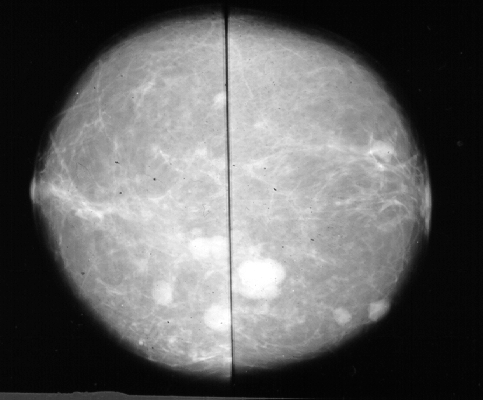

No caso de mamografias é possível identificartumores malignos ou benignos através da análise de sua forma.

As mamografias sao de pacientes diversos e contem tanto tumores diagnosticadoscomo benignos quanto malignos.

Cada imagem foi previamente diagnosticada pelos Departamento de Radiologiada UFF, Hospital Universitario Pedro Hernesto e pelo IRSA-Instituto deRadiologia s.a.